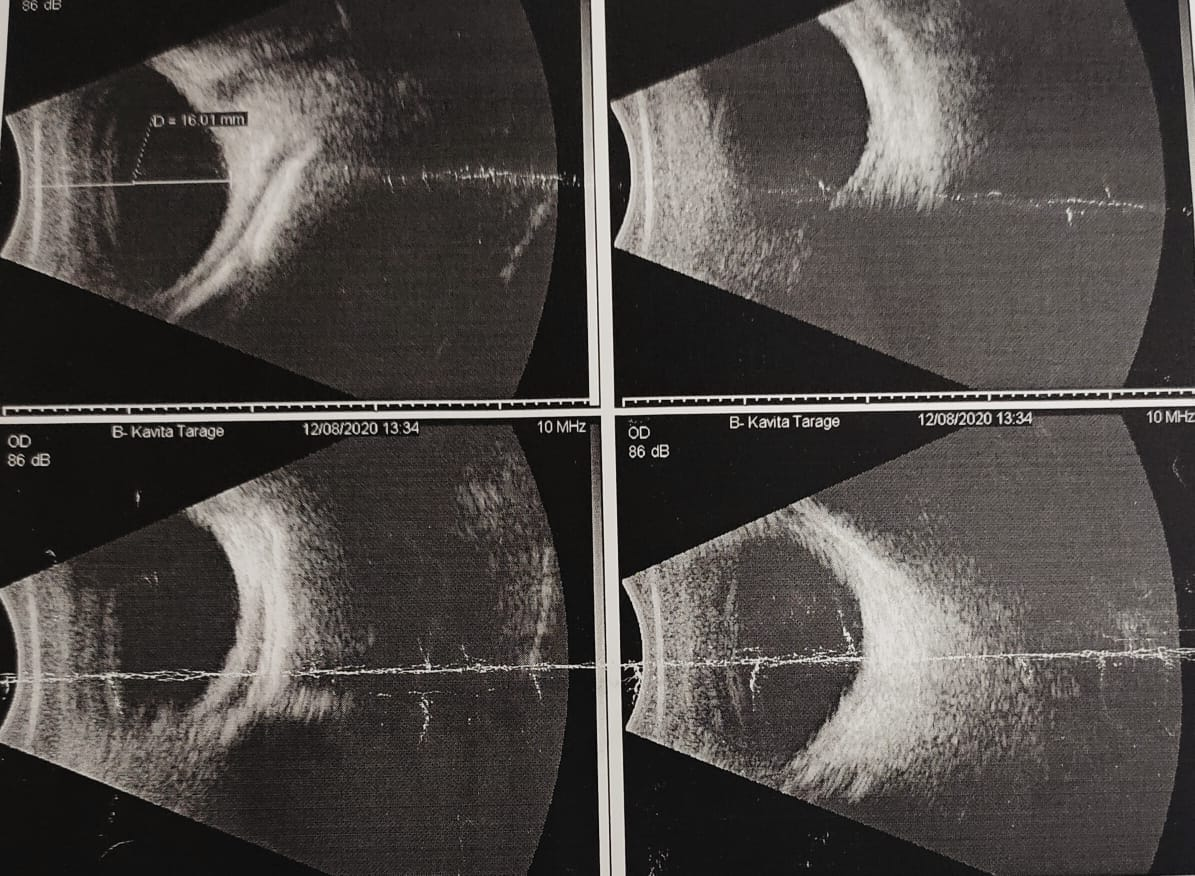

CASE DETAILS: A 10 days old male child is brought by his parents to the ophthalmology OPD with complaints of whitish discolouration of cornea in right eye noted since birth.

Ocular Examination: